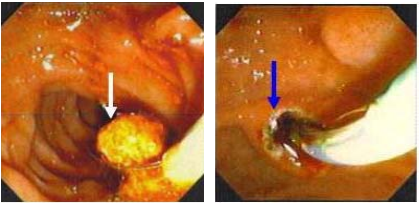

4.2. Nội soi mật - tụy ngược dòng lấy sỏi có hoặc không cắt cơ vòng Oddi

Hình 8. Lấy sỏi qua nội soi mật tụy ngược dòng

(Nguồn: www.ceessentials.net/article41.html)

Các chỉ định:

- Sỏi OMC sau cắt túi mật nội soi

- Sỏi OMC đơn thuần tái phát hay tiên phát trên bệnh nhân có nguy cơ khi mổ mở.

- Viêm tụy cấp do sỏi phần thấp OMC.

- Viêm đường mật cấp nặng do sỏi đường mật có thể lấy được sỏi nhưng thường đặt dẫn lưu mũi mật giảm áp và bơm kháng sinh vào đường mật kết hợp với kháng sinh toàn thân.

Hình 9. Sỏi kẹt Oddi (mũi tên) làm căng phồng nhú Vater